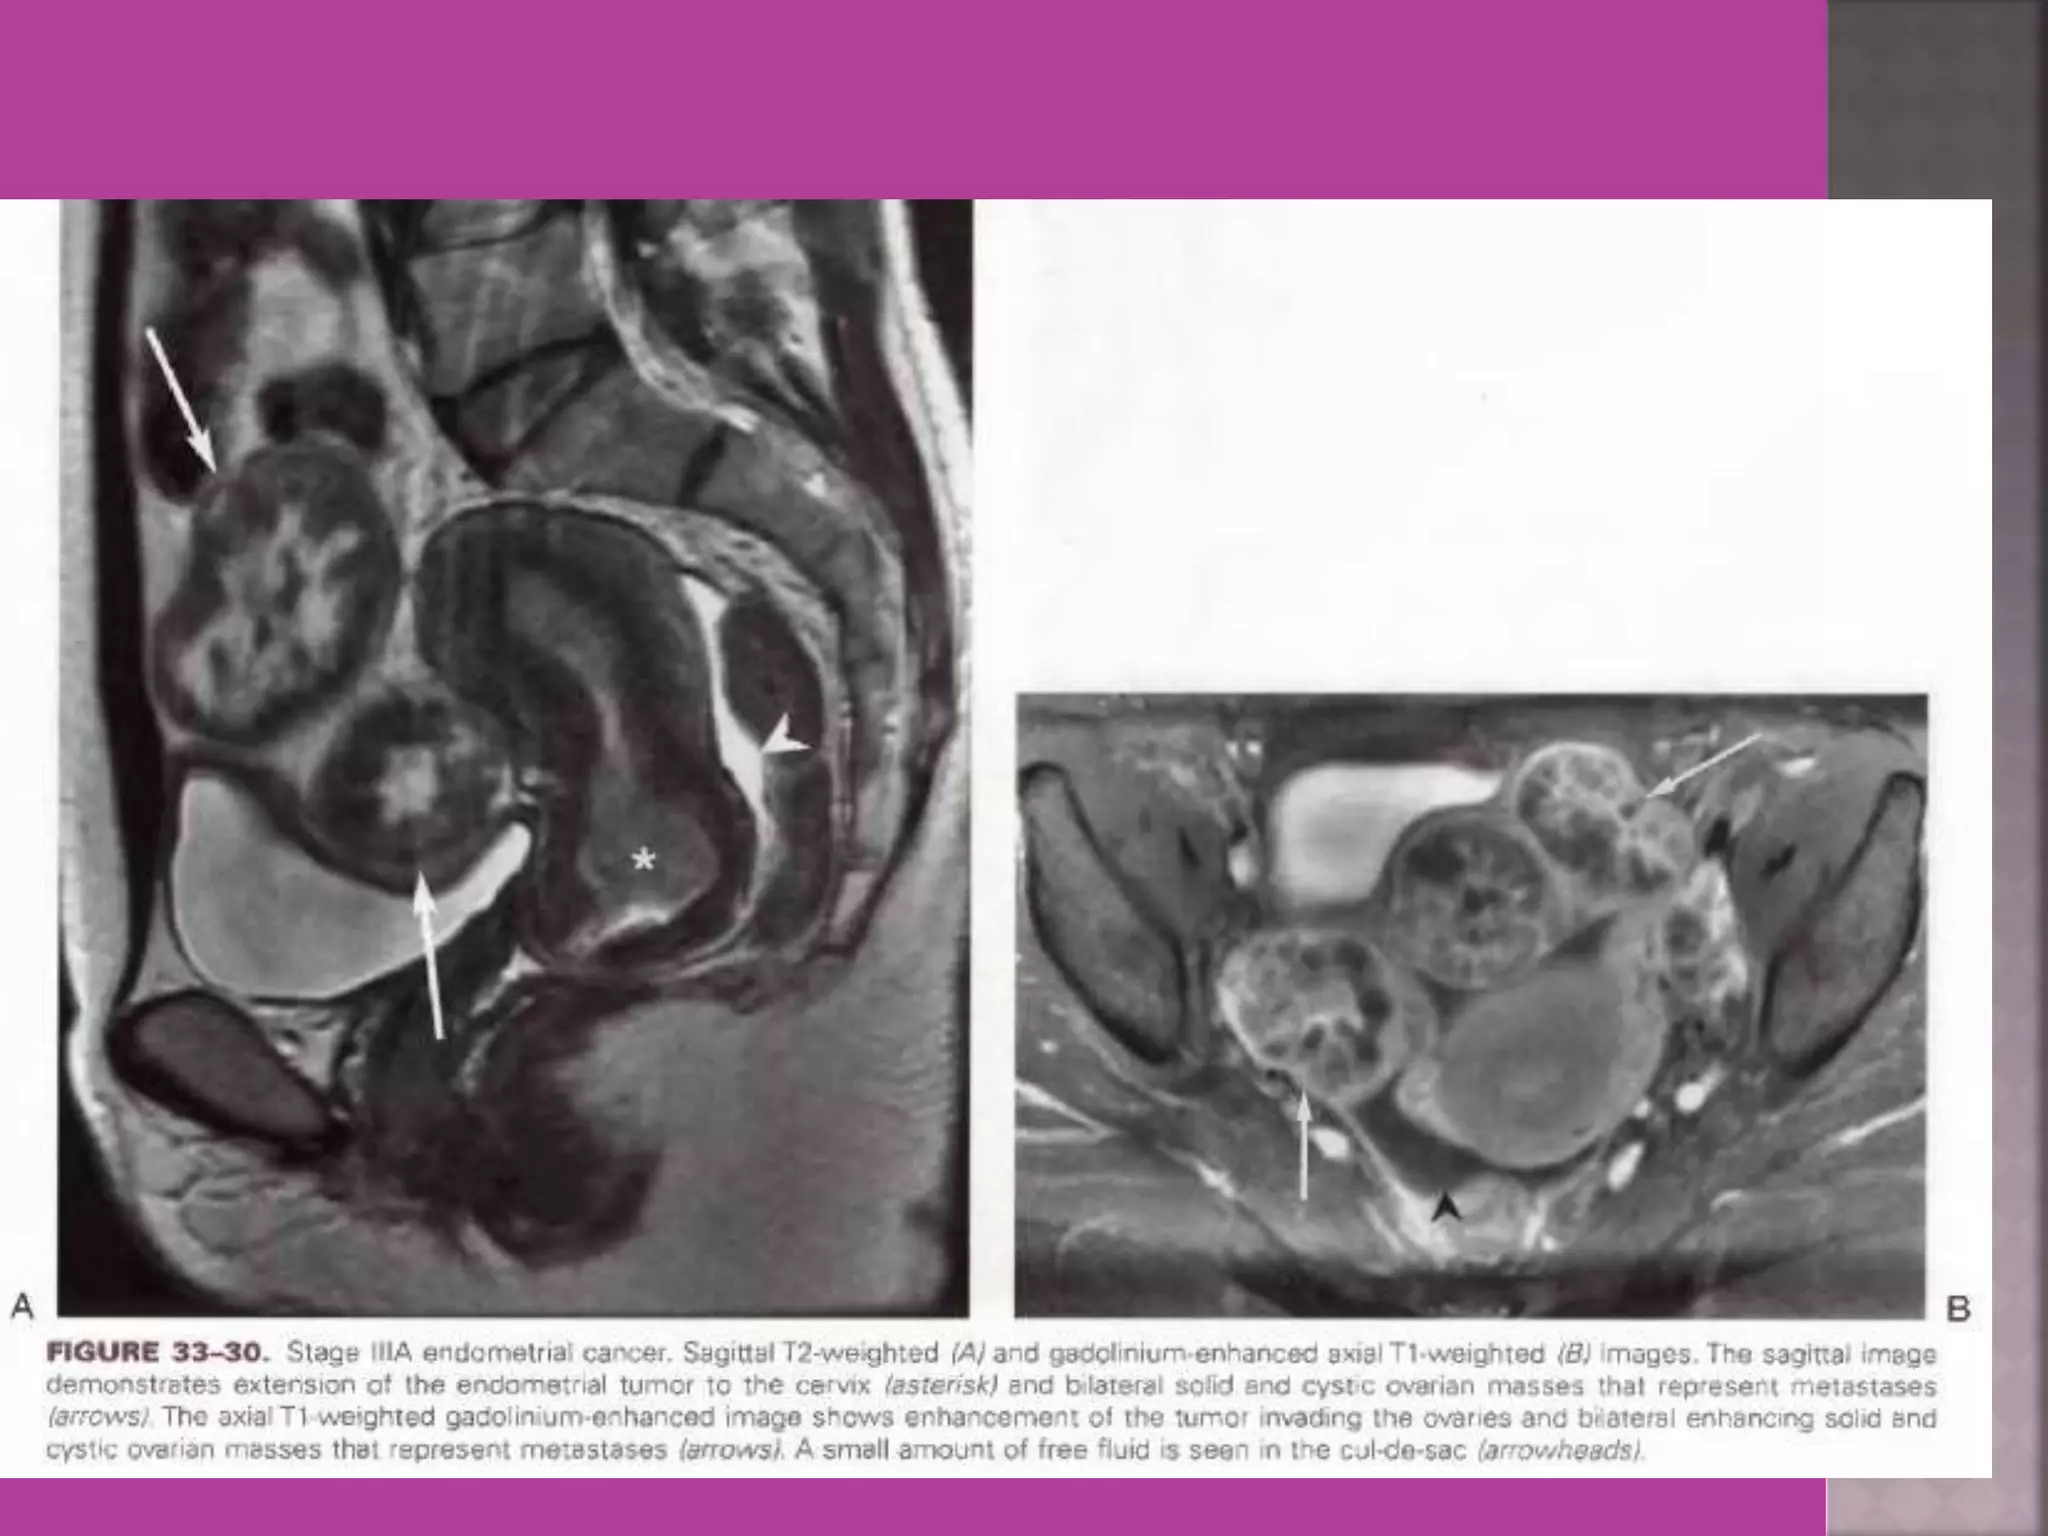

2.Endometrial cancer –Myometrial

invasion, downward extension to cervix.

 Gynaecological cancers--- 1. Cervical cancer –extent of parametrium and pelvic organs , pelvic L.N., Endocervical. 2.Endometrial cancer –Myometrial invasion, downward extension to cervix. 3. ovarian cancer—malignant versus benign mass, ascites , retroperitoneal node > 1cm , Bowel bladder , ano rectal . Parietal peritoneum , liver and or omental metastasis. 4. Pregnancy --- complicated by genital cancers

Endometrial Ca Endo-ca— extending in cervical canal Pelvic Nodes